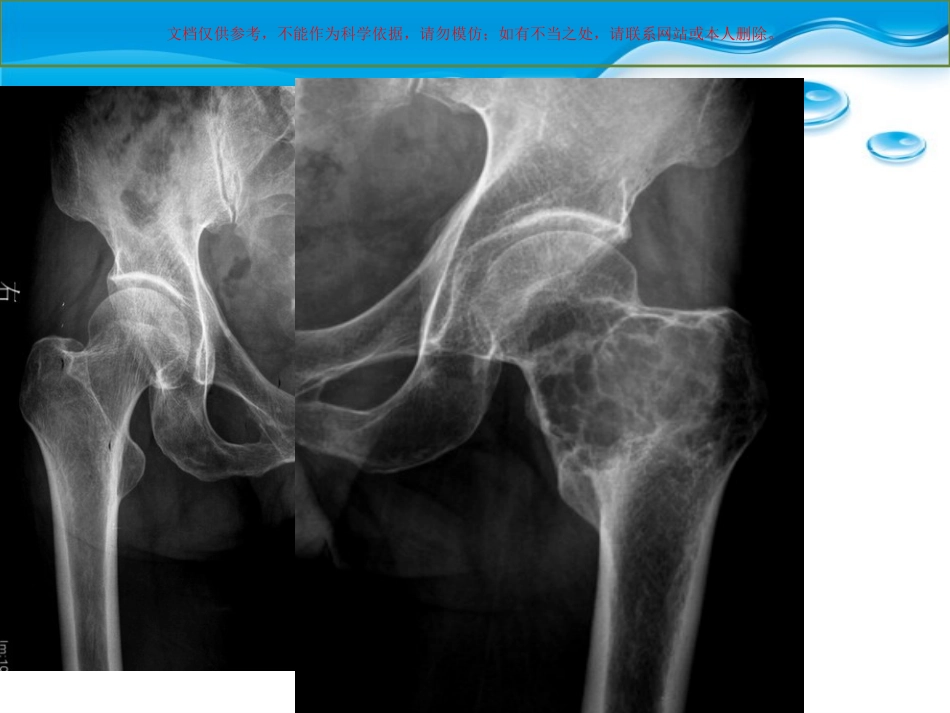

文档仅供参考,不能作为科学依据,请勿模仿;如有不当之处,请联系网站或本人删除。患者一般信息男性56岁3年前无明显诱因出现左髋部疼痛,曾于当地诊所治疗,外用药物(具体不详),近1月自觉疼痛加重,伴跛行,遂往医院就诊;专科检查:左髋部外侧较健侧膨隆,局部压痛(+),髋关节活动受限,皮肤无红肿,左侧腹股沟区淋巴结未触及。文档仅供参考,不能作为科学依据,请勿模仿;如有不当之处,请联系网站或本人删除。文档仅供参考,不能作为科学依据,请勿模仿;如有不当之处,请联系网站或本人删除。轴位T1WIT2WI轴位T1WIT2WI文档仅供参考,不能作为科学依据,请勿模仿;如有不当之处,请联系网站或本人删除。T1WIT2WIT1WIT2WI文档仅供参考,不能作为科学依据,请勿模仿;如有不当之处,请联系网站或本人删除。STIRSTIR文档仅供参考,不能作为科学依据,请勿模仿;如有不当之处,请联系网站或本人删除。轴位T1WIT1WI/C轴位T1WIT1WI/C文档仅供参考,不能作为科学依据,请勿模仿;如有不当之处,请联系网站或本人删除。冠位T1WI/C冠位T1WI/C文档仅供参考,不能作为科学依据,请勿模仿;如有不当之处,请联系网站或本人删除。•MR诊断意见:左侧股骨头、颈及股骨干上端异常信号影,考虑良性骨肿瘤或骨肿瘤样病变,骨巨细胞瘤可能。文档仅供参考,不能作为科学依据,请勿模仿;如有不当之处,请联系网站或本人删除。文档仅供参考,不能作为科学依据,请勿模仿;如有不当之处,请联系网站或本人删除。•手术记录:左侧股骨颈及股骨粗隆部膨隆,后侧为重,骨皮质菲薄不完整,微波灭活后开骨窗刮除白色粘液状肿瘤组织,有软骨光泽。病变累及股骨头下,瘤腔内可见骨性分隔。•术后病理:软骨粘液样纤维瘤文档仅供参考,不能作为科学依据,请勿模仿;如有不当之处,请联系网站或本人删除。•软骨粘液样纤维瘤(Chondromyxoidfibroma)又称纤维粘液样软骨瘤,是一种较少见的良性骨肿瘤,起源于软骨组织,是良性软骨性肿瘤中最少见的一种。WHO统计,占原发性骨肿瘤的1.04%,占良性骨肿瘤的2.31%[1]。由Jaff和Lichtenstein首先报道了此病,并对病理组织学做了详细描述,并予以命名。•【1】王玉凯,主编骨肿瘤X线诊断学:M:北京:人民卫生出版社.1995:106文档仅供参考,不能作为科学依据,请勿模仿;如有不当之处,请联系网站或本人删除。•CMF病理基础:大体所见肿瘤呈圆形或椭圆形,偶尔呈分叶状,切面呈黄白色或灰白色,边缘清楚。瘤内可见纤维条索区、粘液样区、透明软骨区三者呈不同比例相间存在。镜下瘤细胞核多呈星形、椭圆形或梭形,瘤细胞常较为密集,主要由两种基质存在,1、致密的软骨样基质,嗜碱性;2、疏松的粘液样基质,嗜酸性,多以后者为主。粘液样组织可纤维化或变为软骨样组织。【2】免疫组化s-100(+),显示其为软骨类肿瘤。【2】曲亚罡等软骨粘液样纤维瘤CT诊断[J]吉林医学,2004;2:27;文档仅供参考,不能作为科学依据,请勿模仿;如有不当之处,请联系网站或本人删除。•肿瘤有时可见钙化或出血区。但往往钙化较少见,有学者解释为本病是从粘液样组织发生向软骨及胶原纤维转化的特性,而非源于软骨组织后发生粘液样变。【2】•【2】曲亚罡等软骨粘液样纤维瘤CT诊断[J]吉林医学,2004;2:27;文档仅供参考,不能作为科学依据,请勿模仿;如有不当之处,请联系网站或本人删除。•临床资料:本病男性发病率多于女性,约为1.9:1,年龄大多在10-30,占73.2%。发病部位多见长管状骨的干骺端,尤以下肢多见,另外本病也可发生于其他部位,如短管状骨、扁骨、不规则骨等。•本病临床症状较轻微,生长缓慢,主要表现为局部间歇性疼痛,病变范围较大时,可能影响关节功能。表面皮肤多无变化。文档仅供参考,不能作为科学依据,请勿模仿;如有不当之处,请联系网站或本人删除。影像表现•X线:本病多呈偏心性、膨胀性生长,可呈单房或多房性透亮区,肿瘤内可见粗细不一的骨性间隔,数目多少不等,骨皮质菲薄,亦可中断,该病很少有骨膜反应。一般其内缘具有较厚的骨质硬化,其外缘多呈扇形、分叶状。【3】【3】骨肿瘤影像学段承祥、王晨光、李健丁主编,北京科学出版社,2004.7文...